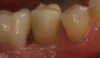

Fig 19. Lingual view of the screw-retained implant crown after placement of the composite “patch.”

Figure 19

Fig 20. Facial view of screw-retained implant crown.

Figure 20

Fig 21. Occlusal view of the screw-retained implant crown.

Figure 21